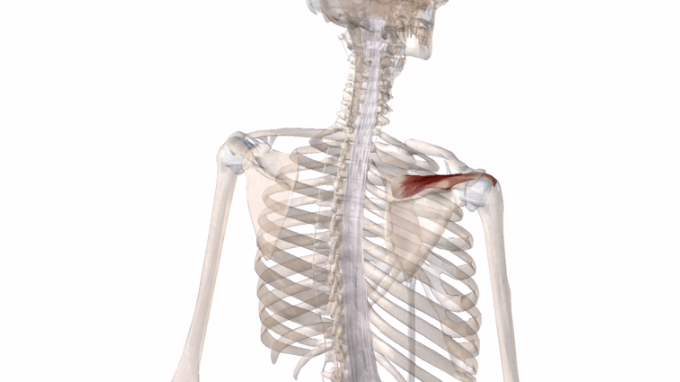

棘上筋↓